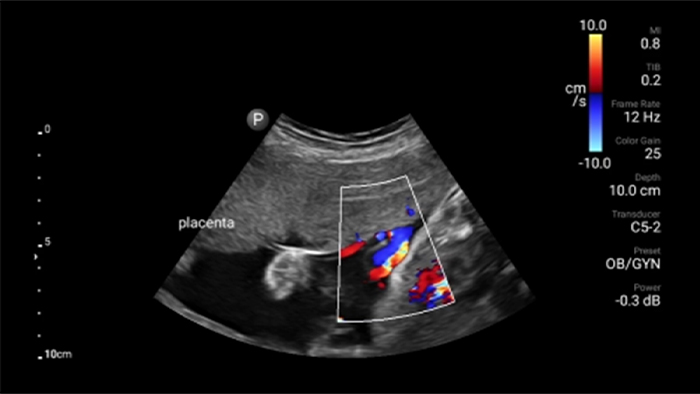

Breng echografie naar het bed

Het gebruik van Lumify aan het bed van uw patiënt kan een waardevol hulpmiddel zijn om de status van de maaginhoud te bepalen en kan hetrisico op pulmonale aspiratie verlagen. Samen kan dit het risico op anesthesiecomplicaties verminderen.